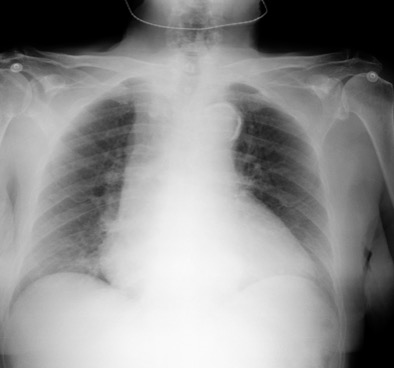

2. En primer lugar, ante la presencia de dolor torácico sugestivo de isquemia miocárdica aguda se debe realizar en los primeros 10 minutos desde la llegada del paciente a urgencias un electrocardiograma para diagnosticar o excluir que se trate de un síndrome coronario agudo con elevación del segmento ST (precisa de terapia de reperfusión mediante fibrinolíticos o angioplastia primaria de manera urgente). También nos será útil para otras patologías. Por otro lado, la radiografía de tórax nos puede aportar información relevante en pacientes con dolor torácico (Tabla 1).

3. En nuestro caso tanto el electrocardiograma que no presenta datos de isquemia miocárdica aguda (descenso del segmento ST menor a 1 mm con onda T negativa asimétrica en I-II-aVL, V5-V6 sugestivo de sobrecarga sistólica de ventrículo izquierdo) como los hallazgos de ensanchamiento del mediastino superior en la radiografía de tórax aumentan la probilidad de que se trate de un síndrome aórtico agudo (SAA). Dada la elevada morbimortalidad que presenta esta entidad es indispensable confirmar o excluir su diagnóstico, siendo para ello fundamental las técnicas de imagen, como son la ecocardiografía (particularmente el ecocardiograma transesofágico) y la tomografía computerizada (TC). En casos de baja probabilidad clínica podría considerarse la determinación del dímero D debido a su elevado valor predictivo negativo para descartar esta entidad. La ecocardiografía es de gran utilidad en pacientes inestables o en casos de alergia al contraste iodado (utilizado en el TC). Por otro lado, el angio-TC (con una sensibilidad y especificidad > del 93 y 83%, respectivamente) es la técnica de imagen más utilizada para el diagnóstico del SAA, en especial en la disección de aorta. Dado que nuestro paciente inicialmente no presentaba deterioro hemodinámico solicitamos un angio-TC (ver imagen) que mostró un aneurisma de aorta ascendente con flap intimal que se origina en aorta ascendente a la salida del tronco braquiocefálico derecho hasta la aorta descendente inmediatamente distal a la salida de la arteria subclavia izquierda, compatible con Disección tipo A de Stanford. Es importante recordar que los SAA puede presentarse de formas muy diversas (infarto agudo de miocardio, insuficiencia aórtica aguda, taponamiento cardíaco, síncope, ictus isquémico o AIT, alteraciones perfusión periférica y crisis hipertensiva).